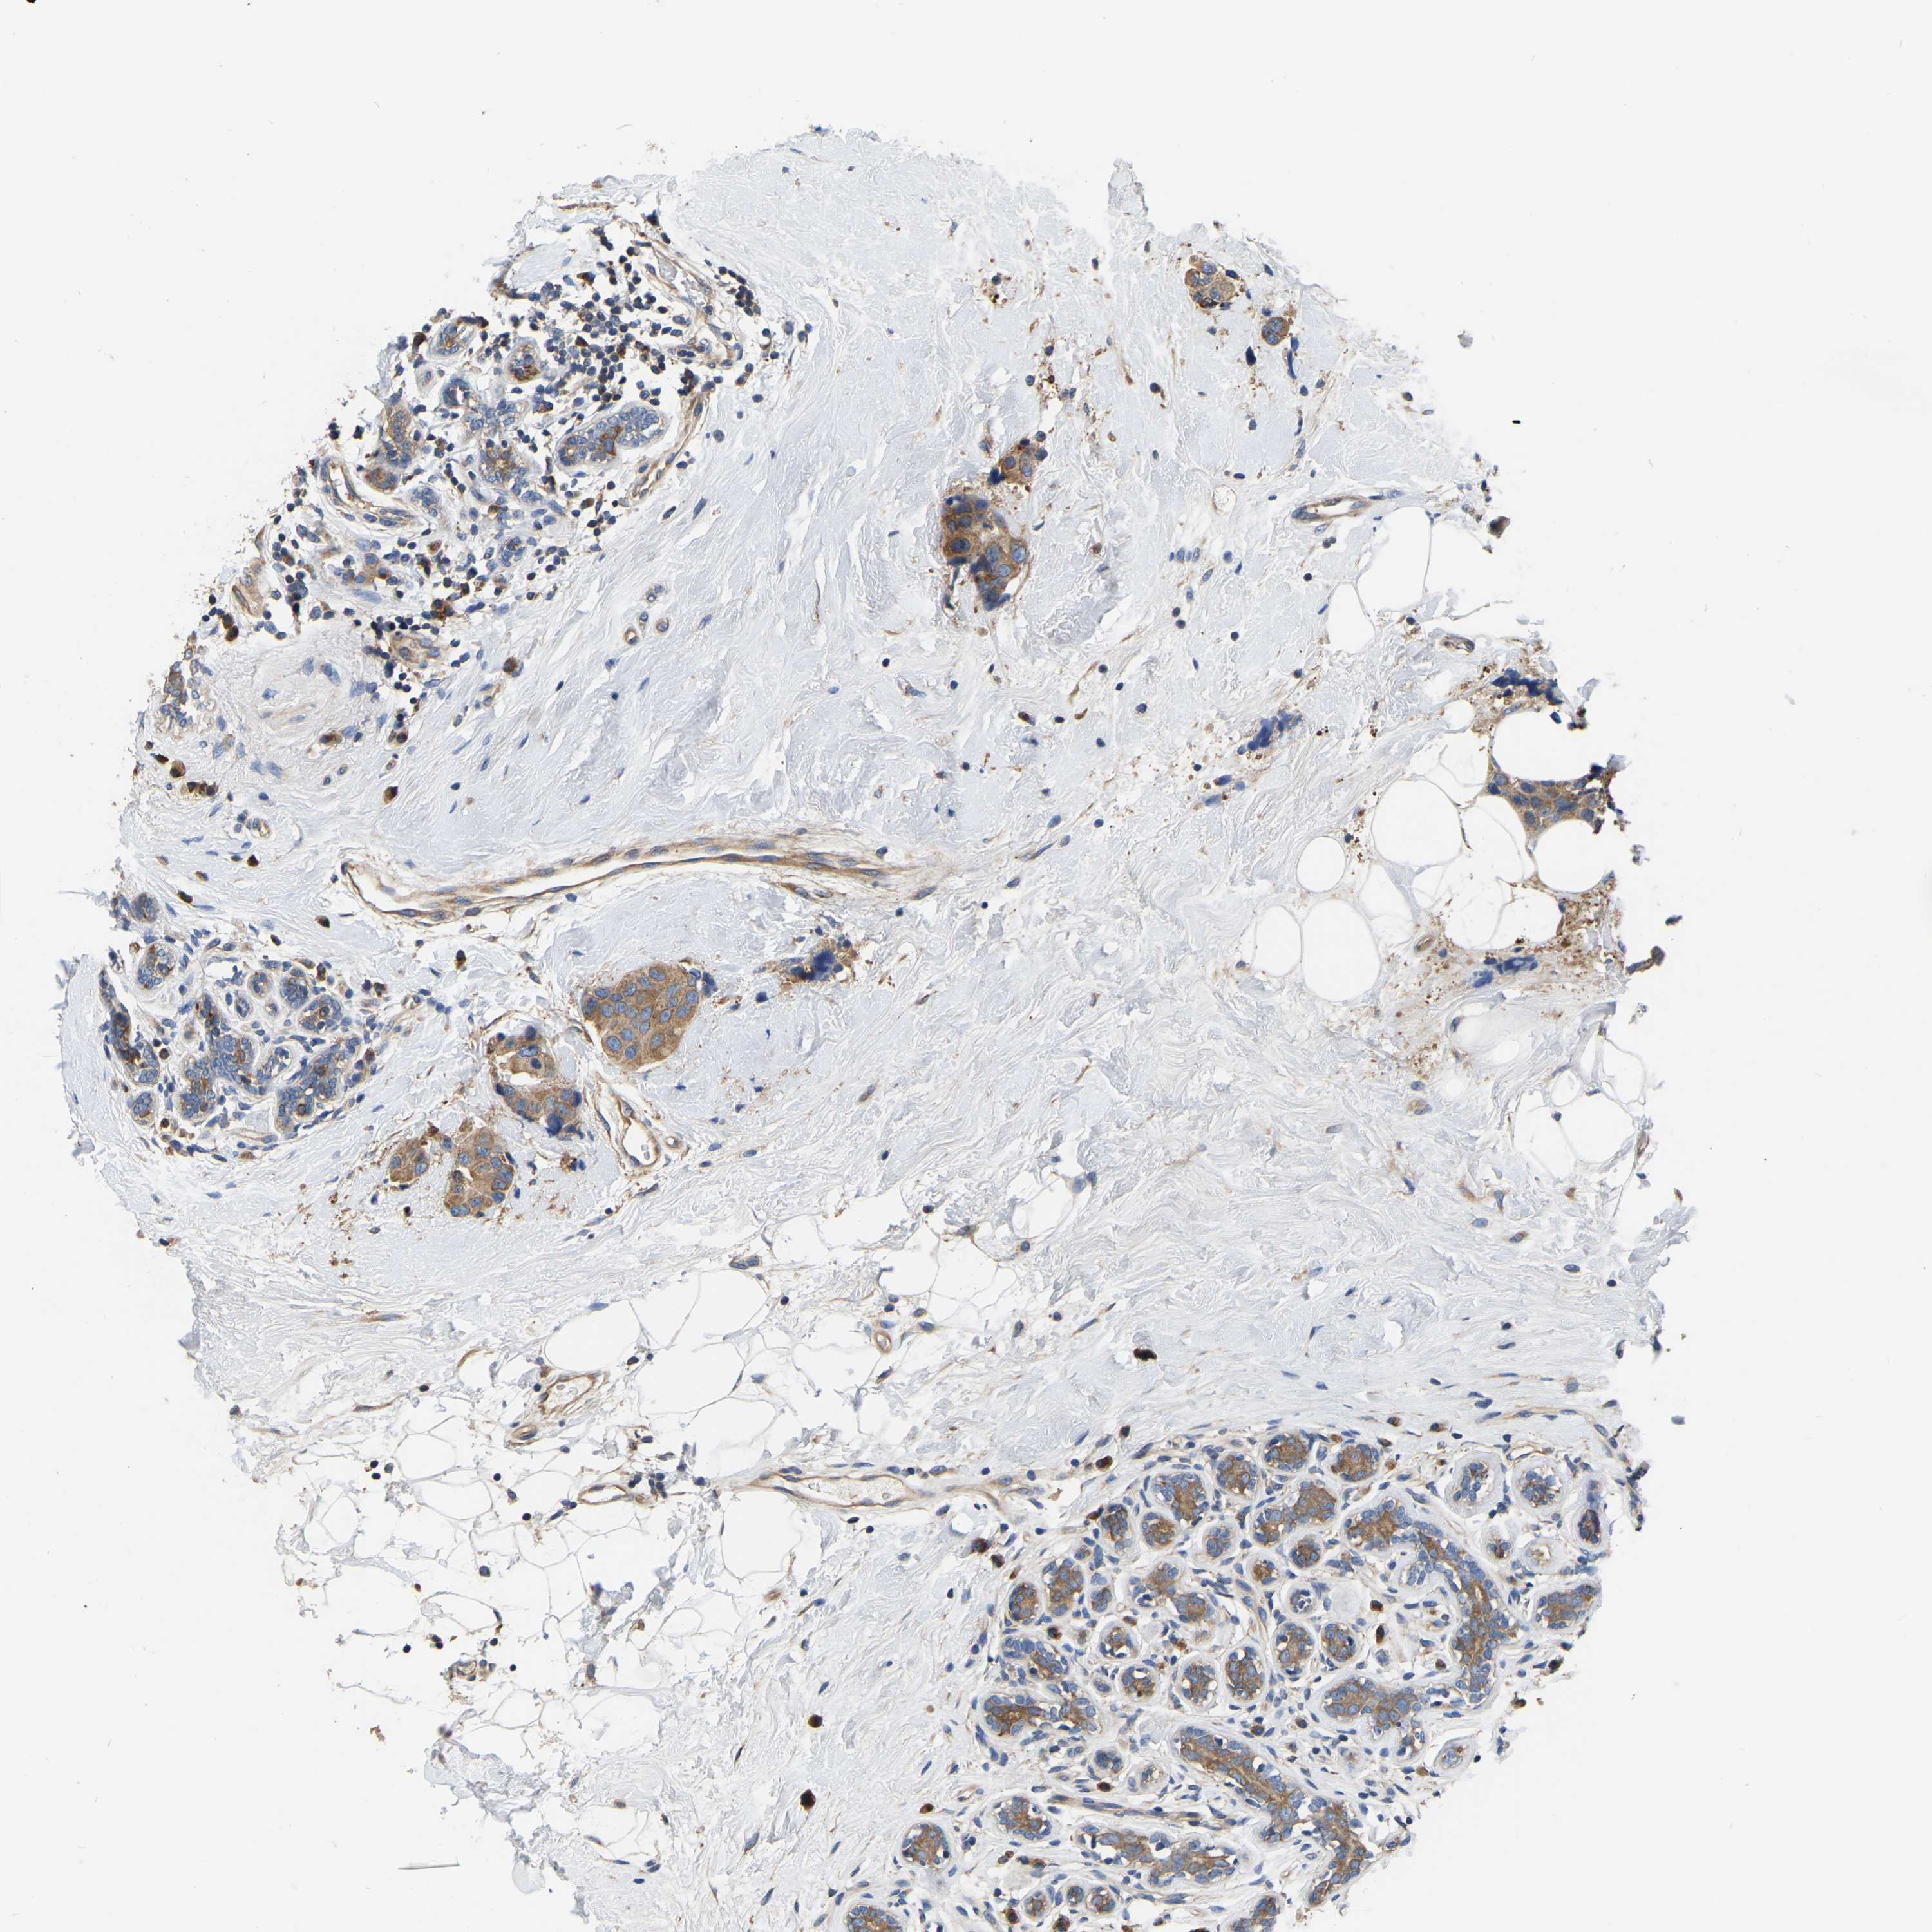

BRCA TCGA BRCA VALIDATION PROTEIN EXPRESSION

Breast cancer

Human cancer